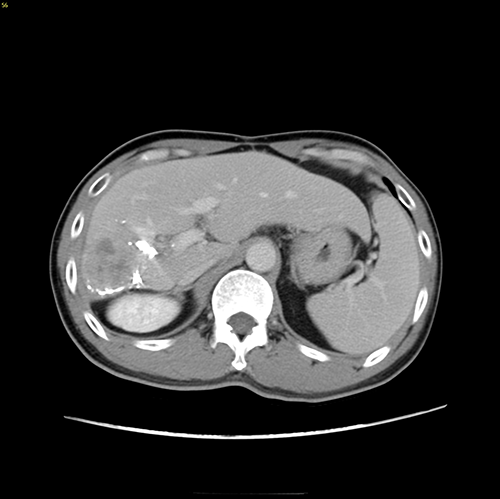

右肝癌复发-门静脉栓塞+肿瘤动脉栓塞后右半肝切除